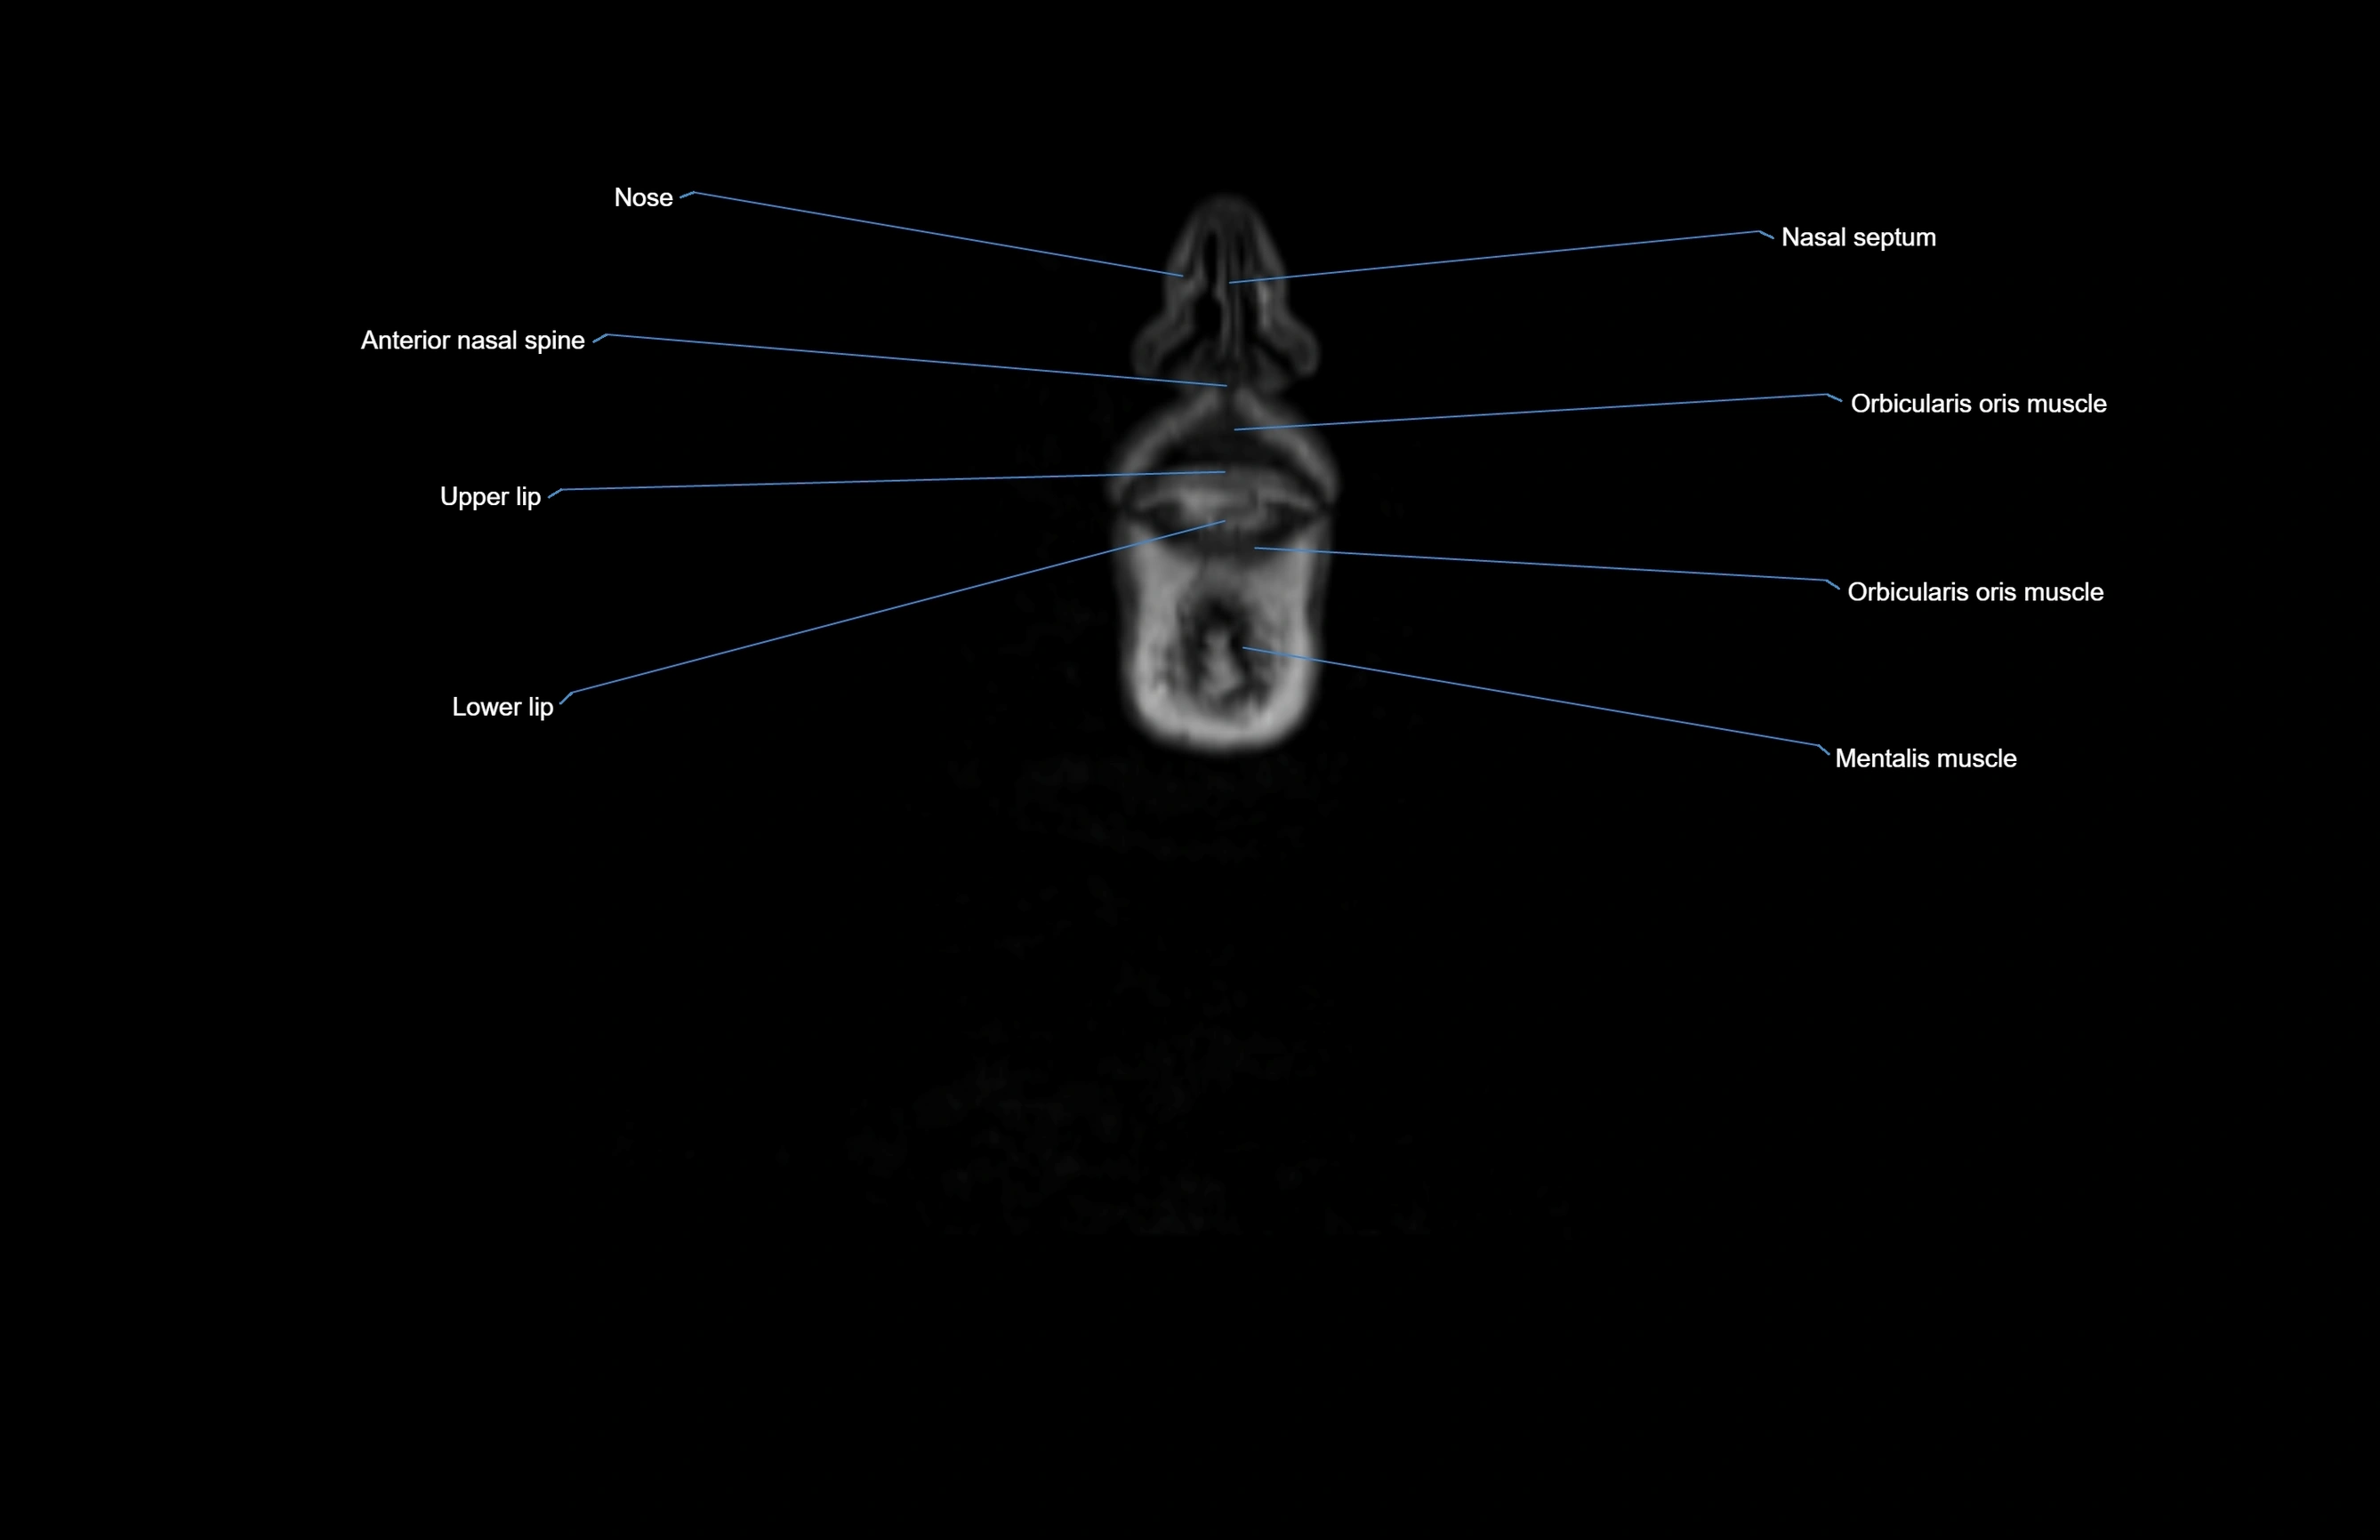

MRI images